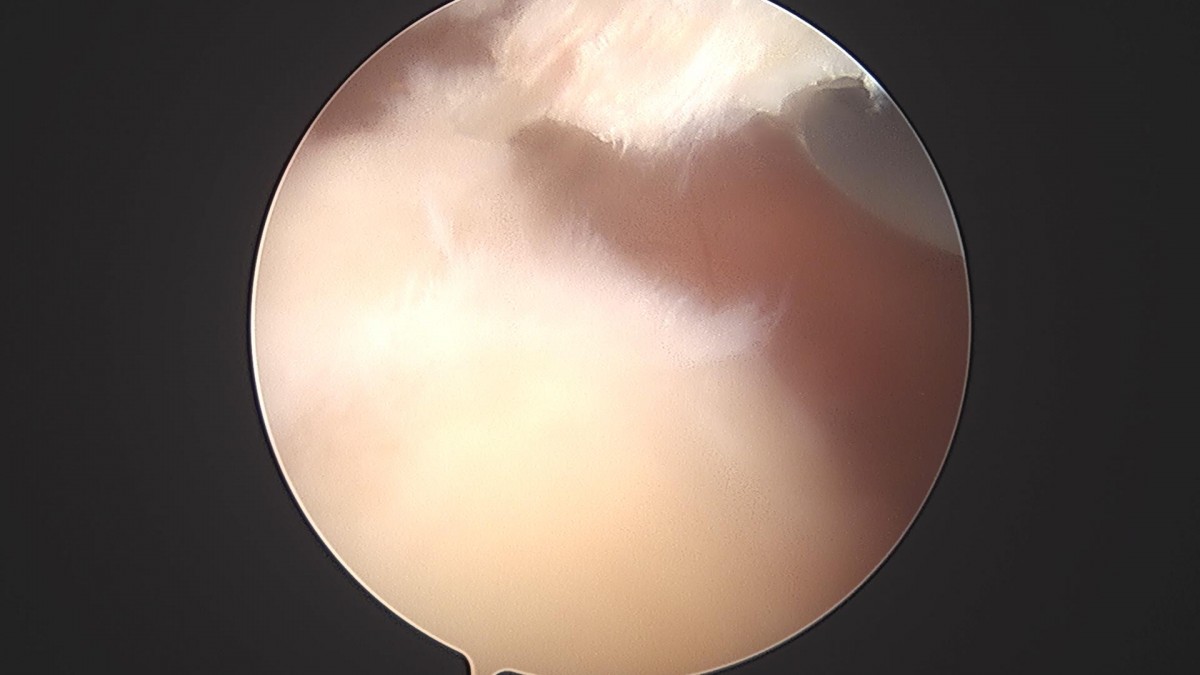

이재상원장님 어깨 견봉하감압술 및 이두박건절제술 류창O 환자